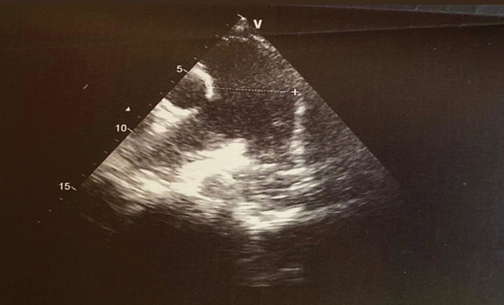

У симптомных пациентов с остаточным тромбозом, предпочтительно выявленным с помощью вентиляционно-перфузионной сцинтиграфии, следует выполнить эхокардиографию для получения информации о вероятности наличия ЛГ. Если вероятность высокая, следует выполнить катетеризацию правых отделов сердца; если низкая, необходимо провести эргоспирометрию. При выявлении картины ограниченной толерантности сердечно-сосудистой системы к физической нагрузке с критериями неэффективности вентиляции, целесообразно выполнить катетеризацию правых отделов сердца во время нагрузки. Диагноз ХТЭБЛ следует устанавливать в случаях с срДЛА <20 мм рт.ст. в покое или >30 мм рт.ст. наряду с ЛСС >3 ед. Вуда во время физической нагрузки.